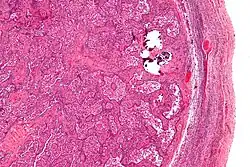

Gonadoblastomas are precancerous lesions that predominantly form in intersex people with gonadal dysgenesis and a Y chromosome.[42][43] This includes conditions such as Swyer syndrome or Turner syndrome with Y chromosome mosaicism.[44][42] These cancer risks are addressed using genetic screening and performing a gonadectomy if necessary.[42]